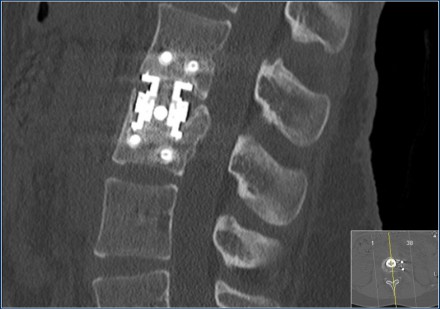

Unfortunately, but not unexpectedly, conservative management failed with near-dislocation.

Finally a posterior spondylodesis was performed.